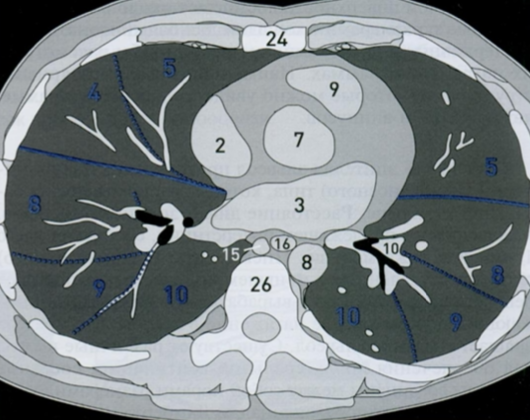

14

Q

КТ грудной клетки №5

Назовите все анатомические структуры, которые Вы знаете, на данном КТ срезе (10).

Найдите грудные позвонки и грудину. Затем правое предсердие, восходящую и нисходящую аорту, легочный ствол, левое предсердие и легочные сосуды, непарную вену и пищевод.

A

26 - грудные позвонки

24 - грудина

2 - правое предсердие

7 - восходящая аорта

9 - легочный ствол

3 - левое предсердие

10 - сосуды легких

8 - нисходящая аорта

15 - непарная вена

16 - пищевод

Синим цветом отмечены номера сегментов.